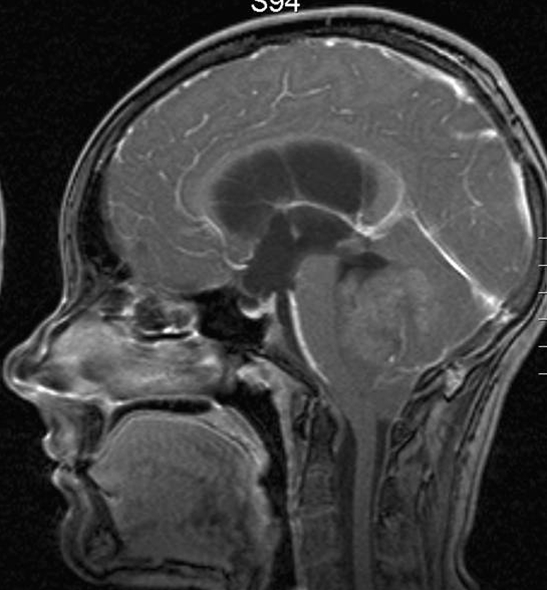

Hjerne, Medulloblastom , MR-scanning

MR-scanning viser et medulloblastom i 2 vinkler (axialt, sagittalt)

Gengivet med tilladelse fra Radiologisk afdeling, Universitetssygehuset Nord-Norge